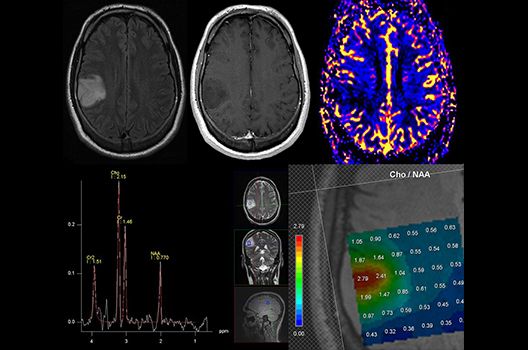

Die Hybridbildgebung mittels PET/MRT spielt insbesondere in der onkologischen Bildgebung eine wichtige Rolle. Eine mögliche Fragestellung ist die Unterscheidung zwischen einem Tumorrezidiv oder therapeutisch assoziierten Veränderungen insbesondere dann, wenn diese Frage mittels MRT alleine nicht beantwortet werden kann.

Die bildgebende Diagnostik und Verlaufsbeurteilung von Tumoren des Nervensystems ist einer der klinischen und Forschungsschwerpunkte unserer Abteilung. Eine besondere Bedeutung kommt der Hybrid-Bildgebung zu. Das Universitätsklinikum verfügt über einen integrierten Ganzkörper-PET/MRT-Scanner, der die Vorteile der MRT-Bildgebung und der Positronenemissionstherapie (PET) vereinigt. Aufgrund der langjährigen klinischen Arbeit und Forschungstätigkeit mit diesem Gerät hat die Neuroradiologie Tübingen maßgeblich zur Etablierung dieses Verfahrens beigetragen. Auch weiterhin forschen wir intensiv an neuen Methoden zur frühen Einordnung von Tumoren und insbesondere Tumorrezidiven, die mit anderen Methoden häufig nicht erfasst werden können.